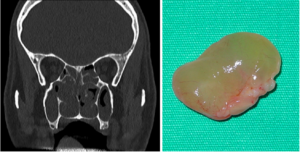

- Görüntüleme/Laboratuvar: Gerekirse sinüs tomografisi veya kan testleri (vitamin düzeyleri vb.) istenebilir (Şekil 3).

Şekil 3. Tüm sinüsleri ve burun boşluklarını dolduran polip kitlelerinin bilgisayarlı tomografideki görünümü (solda) ve ameliyatta çıkarılmış polip kitlelerinden biri (sağda).